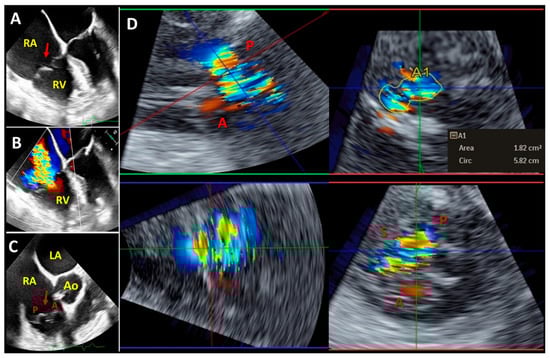

5. Three-Dimensional Echocardiography of the Right Ventricle and Tricuspid Valve

6. Added Value of 3D Echocardiography Compared to 2D Echocardiography in the Assessment of the Right Ventricle

6.2. RV Volume Overload